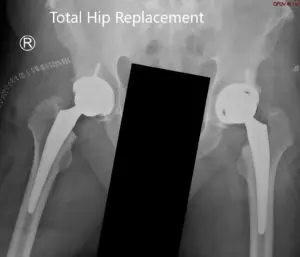

Radiografía postoperatoria que muestra la vista AP de la pelvis con ambas caderas.